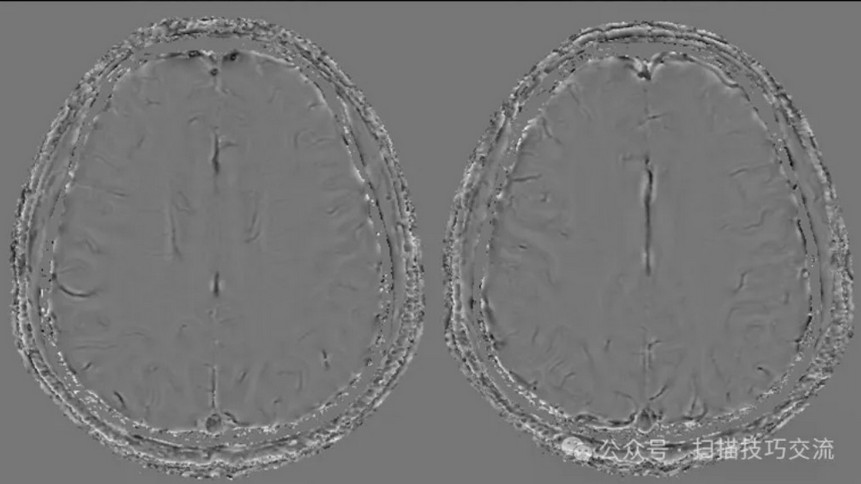

临床申请:颅脑平扫,静脉成像,磁敏感成像,颅内静脉血管黑血成像。

颅内静脉黑血成像,CUBE T1fs w/o +c,静脉窦未见异常。